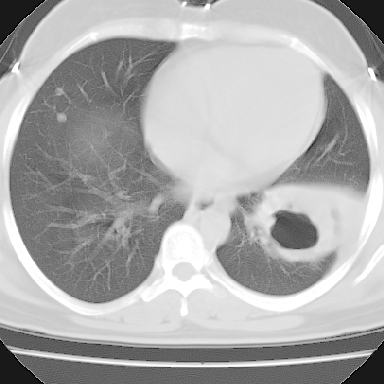

左下肺肿块影,内可以见小泡征,并见厚壁空洞形成,洞内缘凹凸不平,可见壁结节。靠近胸膜侧可见胸膜凹陷征。左侧胸腔内可见少量低密度积液影。双肺可见多发性小结节影。

考虑:左下肺癌性空洞伴两肺转移

左下肺肿块影,内可以见小泡征,并见厚壁空洞形成,洞内缘可见壁结节。靠近胸膜侧可见胸膜肥厚粘连。双肺可见多发性小结节影。

考虑:左下空洞性肺癌伴两肺转移